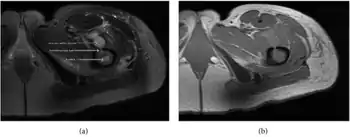

| a,b) MRI showing the Brodie's abscess in the left proximal femur | |

A Brodie abscess is a subacute osteomyelitis, which may persist for years before progressing to a chronic, frank osteomyelitis. Classically, this may present after progression to a draining abscess extending from the tibia out through the skin. Occasionally acute osteomyelitis may be contained to a localized area and walled off by fibrous and granulation tissue.